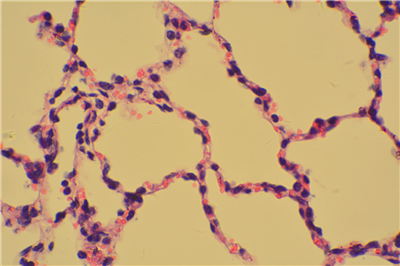

HE染色

苏木精 — 伊红染色法 ( hematoxylin-eosin staining ) ,简称HE染色法 ,石蜡切片技术里常用的染色法之一 。苏木精染液为碱性 ,主要使细胞核内的染色质与胞质内的核酸着紫蓝色 ;伊红为酸性染料 ,主要使细胞质和细胞外基质中的成分着红色 。HE染色法是组织学、胚胎学、病理学教学与科研中基本、使用广泛的技术方法。